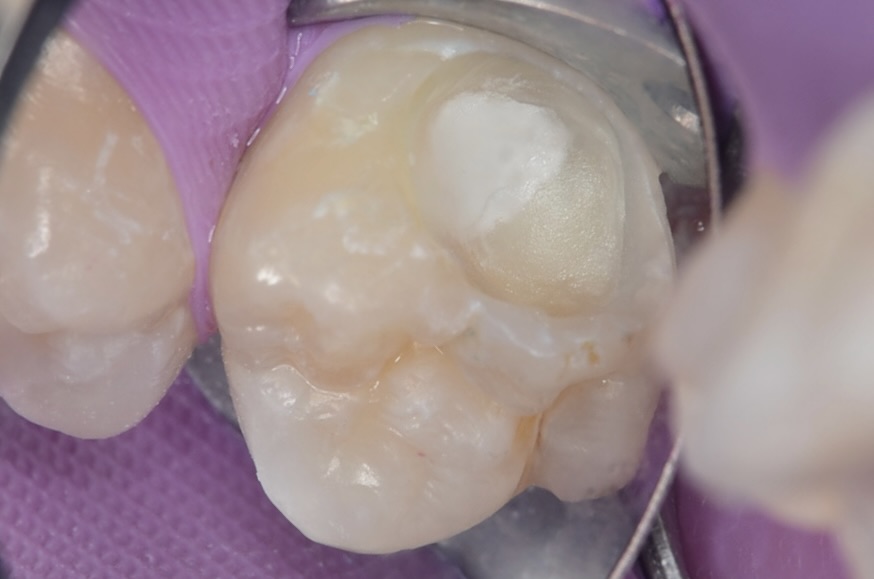

MTAセメント

-

スーパーボンド

MTAセメントは硬化に時間がかかるので、8分で硬化し、象牙質に強力に接着するスーパーボンドでMTAセメントを覆います。 -

ダイレクトボンディング

フロワブルレジンの表面張力を利用して滑らかに充填します。 -